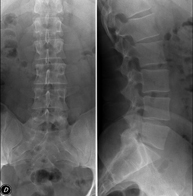

- Lumbar spine X-ray

This technique uses X-ray rendered imaging to examine the lumbar spine. Indicated for: sciatica, trauma, lower back pain.